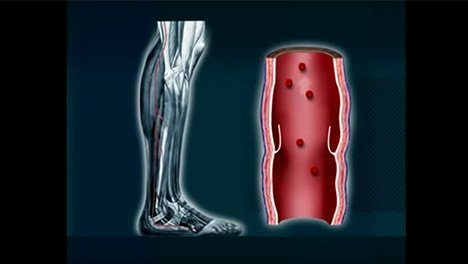

Veins are responsible for returning blood to the heart. But when they become damaged, and are unable to return blood effectively, they can cause complications throughout the body, including increased pressure on vessel walls and pooling of blood in the legs.1 Several types of deep venous disease (DVD) conditions exist including venous compression, deep venous obstruction (DVO), deep venous insufficiency (DVI), nonthrombotic iliac vein lesions (NIVL), popliteal entrapment syndrome, and thoracic outlet syndrome.2 Each condition leads to the compression of veins in different parts of the body and can be either acute or chronic. Over time, these conditions can lead to chronic swelling and various vein problems and can put you at risk for deep vein thrombosis (DVT). Learn more about the deep venous disease symptoms and how DVD can be treated.

Deep venous disease (DVD) may cause uncomfortable swelling in the legs, feet and ankles.

Deep venous insufficiency can cause pooling of blood in the legs and feet causing swelling and pain especially after prolonged standing. Take the step and learn from other patients what the road to recovery is like.